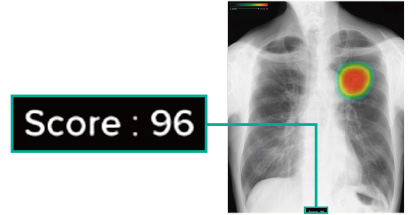

胸部レントゲン検査